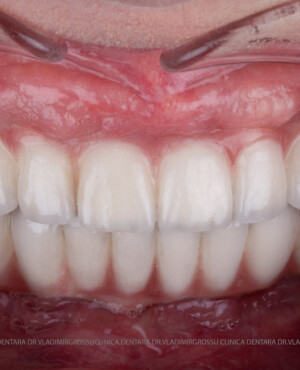

Această metodă este recomandată pacienților edentați total sau celor cu lipsuri dentare multiple. Procedura se realizează într-o singură etapă, iar pacientul primește proteza provizorie în ziua următoare intervenției. De regulă, proteza provizorie este realizată din masă plastică frezată. Suturile se îndepărtează după 5-7 zile.

La aproximativ 6 luni de la prima etapă, pacientul revine pentru protezarea definitivă. În această fază, medicul lucrează la nivelul multiunit-urilor și nu direct pe implanturi, ceea ce reduce riscurile pentru implant în etapa protetică.